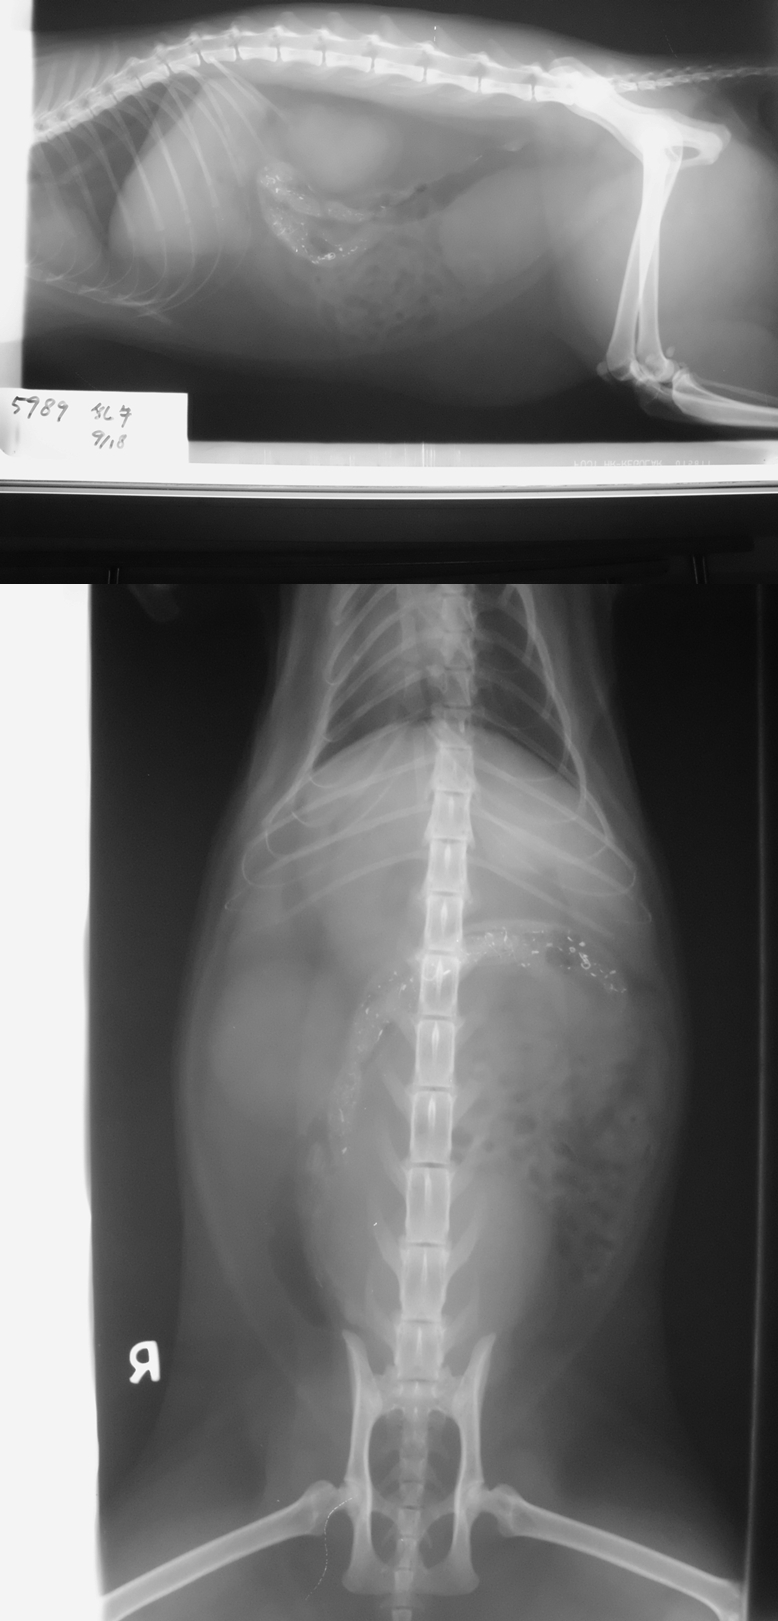

- 編號: 3174

主題: 前鎮明道路血尿的乳牛貓 申請者姓名: 劉雅雲 花色: 申請日期: 2013-10-26 00:23:57 申請者部落格: 申請者臉書網址: 所在縣市/合作醫院: 高雄市/樂生動物醫院 治療費用: 14100元 需求人數: 16人 已結案 (2014-01-10 17:58:20) 報名人員: Kuen-Lin Tsai(已付款)、小娃(已付款)、收夕(已付款)、謝琦琦(已付款)、謝琦琦、Ou Han(已付款)、Leah(已付款)、JasmineC x2(已付款)、M&M(已付款)、Vincent Ho(已付款)、葉小姐(已付款)、Jason Liu(已付款)、ERic YU(已付款)、周小蕾(已付款)、Example Chen(已付款)、chiaowho(已付款)、 候補人員: 動物病情說明: 這是餵養區周圍的貓, 已有結紮, 偶爾會出現, 但最近幾次看到他走路慢慢的, 屁股濕濕,不太吃, 所以誘捕到醫院檢查, 發現有血尿及尿毒症,口腔有潰瘍及牙結石. 經過了治療終於康復了. 感謝大家的協助.

8.X光 300*2= 600

9.超音波 500